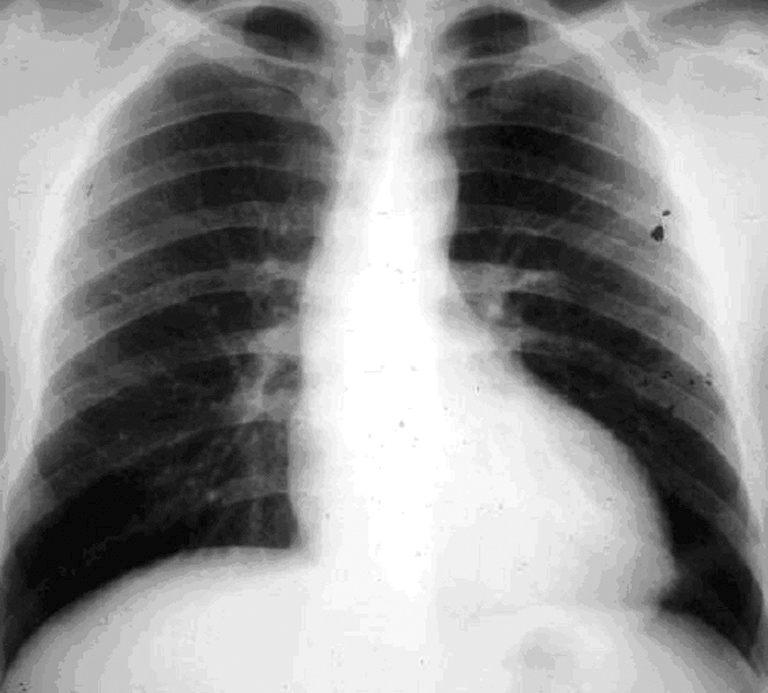

Cas clinique : Figure 1